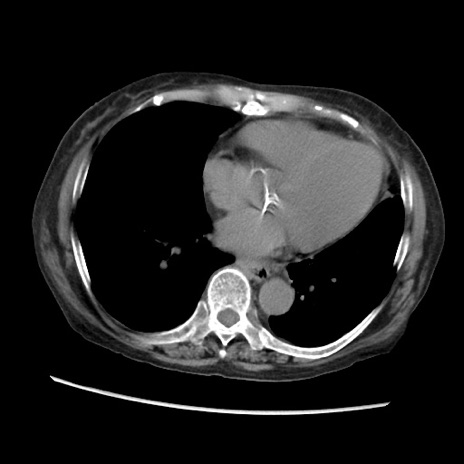

症例31(横断像)

【症例】80歳代 女性

【主訴】腹部膨満感

【現病歴】他院にて肝硬変にてフォロー中。1週間前から便秘、腹部膨満感、臍部腫瘤あり受診となる。

【既往歴】肝硬変

【身体所見】腹部膨隆あり、皮膚変化なし、疼痛なし。

【データ】WBC 4600、CRP 0.25